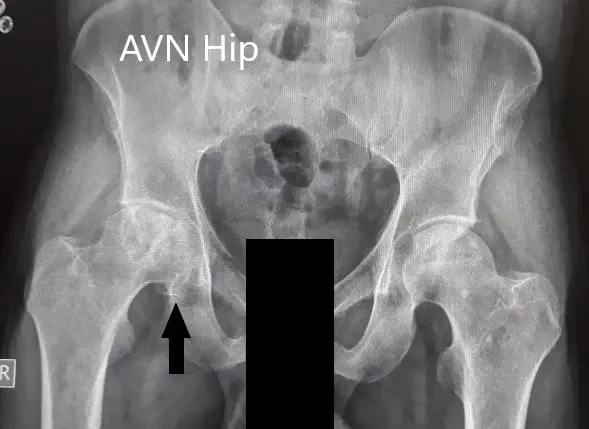

Imaging was acquired in the form of X-Rays which suggested the collapse of the femoral head on the right side. There was a loss of sphericity of the right hip with sclerosis and subchondral cysts. The left hip had an intact contour. MRI was advised of the pelvis with both hips.

Preoperative X-Ray of the pelvis with both hips in anteroposterior and frog-legged lateral views